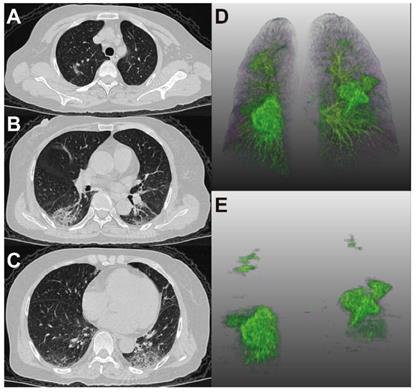

Figure 4 and 5 showed two typical cases with and without clinical endpoint during hospitalization.

Figure 5

66-year-old woman with coronavirus disease 2019. A-C. Non-contrast CT was performed on day of admission. D. Three-dimensional volume-rendered reconstruction shows the distribution of the opacities. E. Pulmonary opacities segmented by AI system. The patient showed fever and cough at admission. Patient did not reach clinical endpoint during hospitalization. Lung CT images showed that consolidation and ground-glass opacities mainly distributed in the lower lungs.

Theranostics Image